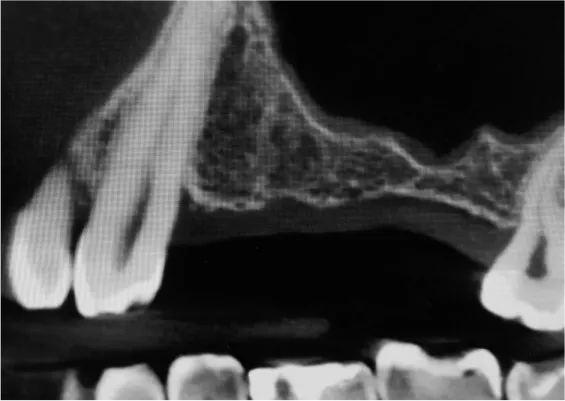

Odbudowa kostna w ODCINKACH BOCZNYCH SZCZĘK - PODNIESIENIE DNA ZATOKI SZCZĘKOWEJ (SINUS LIFT)

Technika odbudowy kostnej stosowana w celu wszczepienia implantów w zanikłe, boczne odcinki szczęk. Najistotniejszą przyczyną utraty kości wyrostka zębodołowego szczęk w odcinkach bocznych są ekstrakcje zębów. Niedostatek kości w wymiarze pionowym stanowi szczególną anatomiczną przeszkodę dla implantacji w okolicy dna zatoki szczękowej. Chcąc odbudować uzębienie i przywrócić funkcję żucia, trzeba podjąć wieloetapowe leczenie rekonstrukcyjne.

Zabiegiem, który rozwiązuje ten problem, jestpodniesienie dna zatoki szczękowej (sinus lift), czyli odbudowa kostna w okolicy zębów trzonowych. Ubytek kości uzupełniany jest materiałem kościotwórczym, który układany jest pod błoną wyścielającą zatokę szczękową, zwaną membraną Schneidera. Zmniejszając objętość zatoki szczękowej, tworzy się tym samym stabilną strukturę kostną, umożliwiającą zabieg implantacji wszczepów śródkostnych.